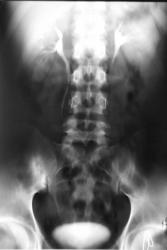

нефрозонограмма 15 минут

Изображение не могу перевернуть

Итак, функция с обеих сторон обычно, как "надо". Нефрографический эффект с обеих сторон, вполне удовлетворительный, что свидетельствует о хорошой функциональной способности почечной паренхимы. Справа определяется "недостаточное" контрастирование лоханки и стойкие спазмы шеек чашечек, что косвенным образом указывает на воспалительный процесс.

На следующем, представленном Вами снимке, четко визуализируется "деформация полой системы" левой почки, о чём свидетельствует небезысвестный феномен Hodson, кроме всего прочего определяются булавовидно эктазированные малые чашечки слева.